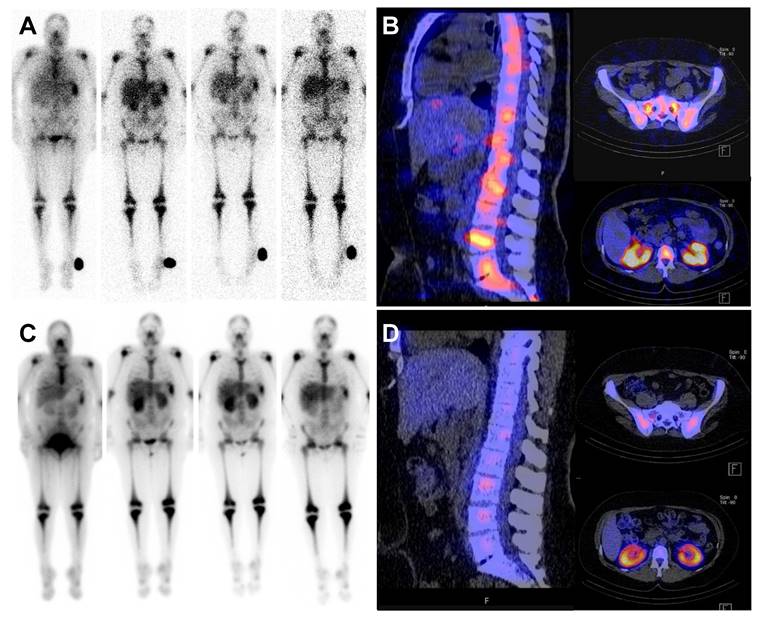

Figure 3

Pre- and post-therapeutic dosimetry. Pre- and post-therapeutic scintigraphy and SPECT/CT imaging of a 47 year old patient with refractory AML. Pre-therapeutic whole-body scintigraphy at 1 hour post injection (p.i.); 22h p.i.; 48h p.i. and 6 days p.i. (A, from left to right) for dosimetry including fused SPECT/CT (B). Post-therapeutic whole-body scintigraphy at 2 h, 24 h, 48 h and 6 d after administration of 14.4 Gbq [177Lu]Pentixather (C) and fused SPECT/CT (D).